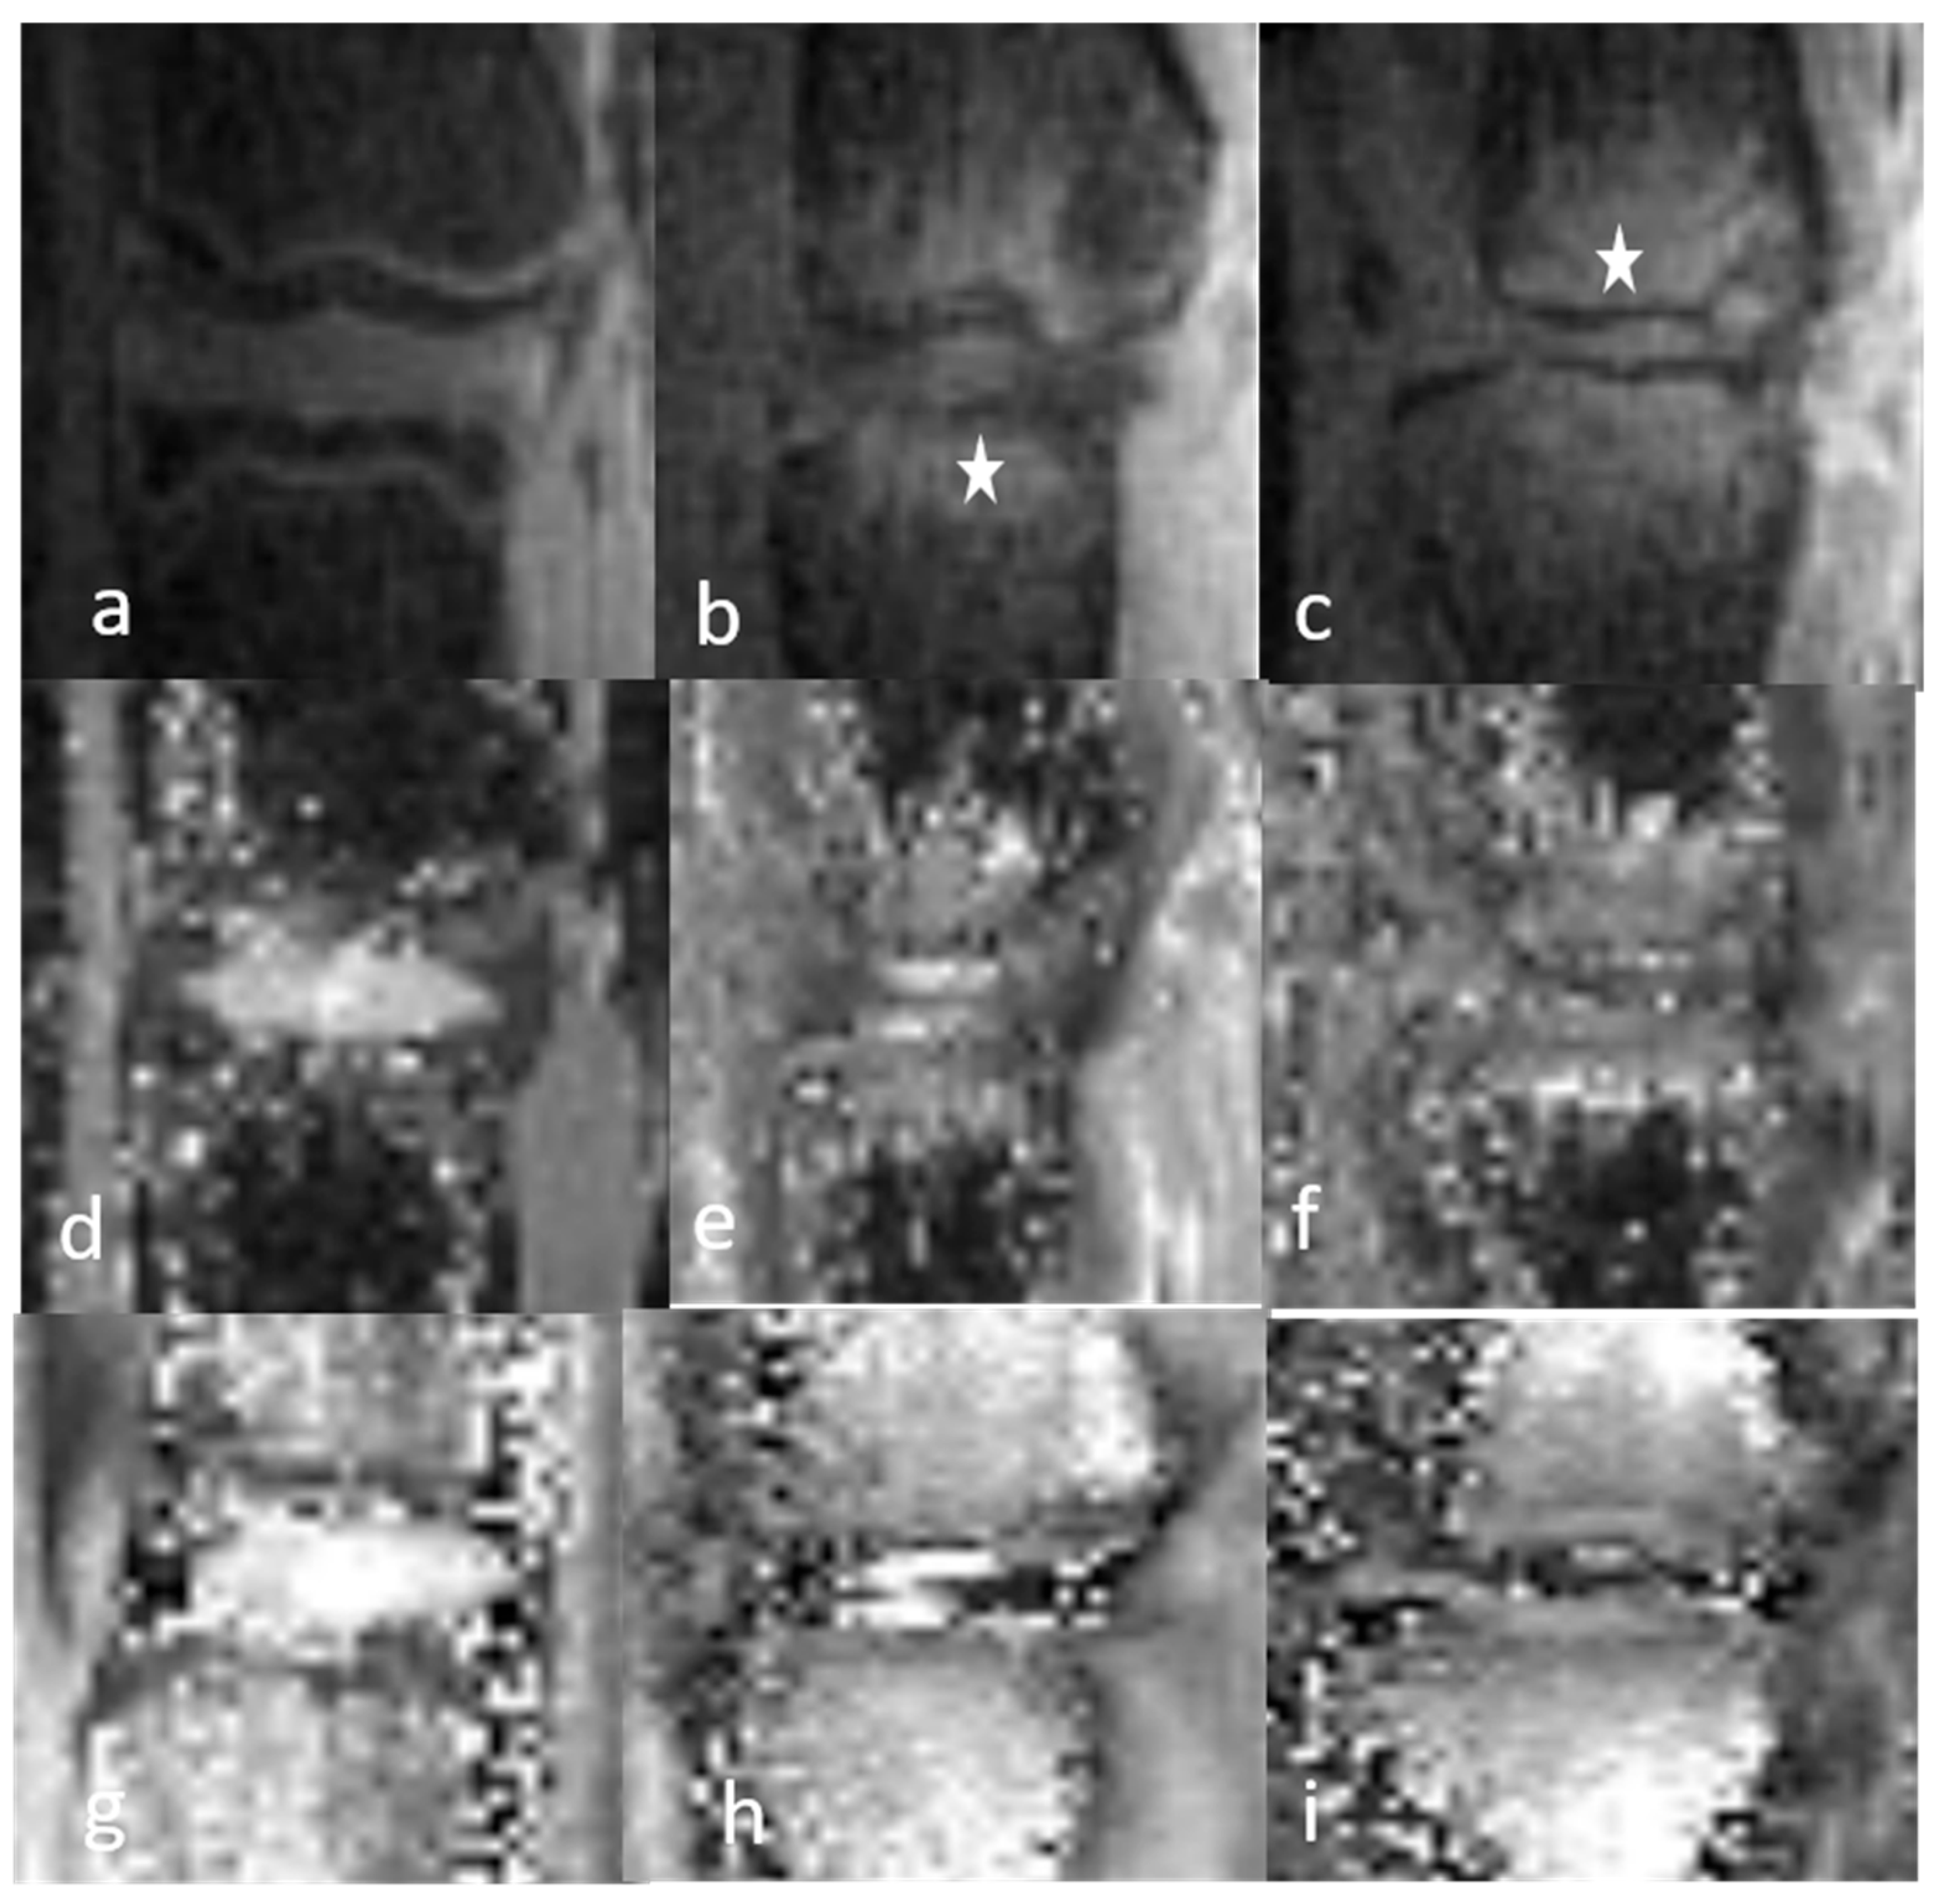

3.1.1. Qualitative Analysis of the Normal DVC (Table 1 and Table 2)

3.1.2. Qualitative Analysis of the DVC in DDD Rats (Table 3)